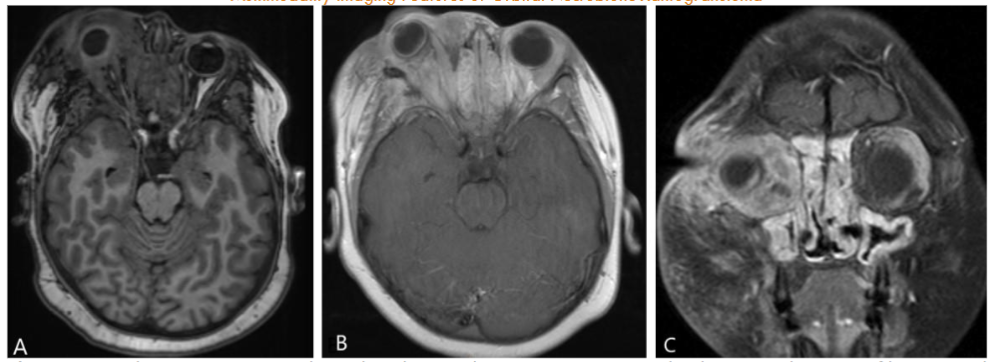

Orbital MRI provided a clearer characterization of diffuse retro-orbital soft tissue thickening, involving the fat, extraocular muscles, and lacrimal glands, leading to pronounced right orbital proptosis and globe eversion. The right globe was flattened with optic nerve stretching. The retrobulbar mass extended posteriorly into the orbital apex without cavernous sinus involvement, and there was also further extension into the lateral face, affecting the temporalis muscle.